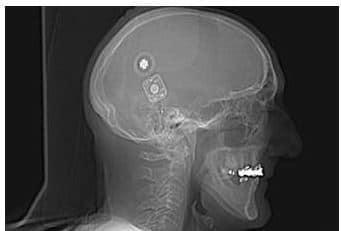

https://www.chu-media.info/article/orl-implant-auditif-insere-par-chirurgie-robot-assistee-1ere-mondiale/

orlimplantparchirurgierobot